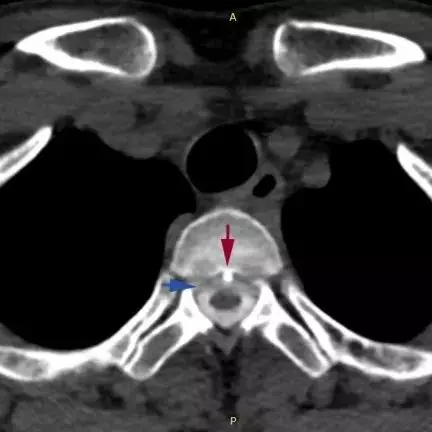

宋先生的脊柱磁共振檢查

可見第2、3胸椎之間有「骨刺」形成(紅箭頭)

刺破硬脊髓膜,造成腦脊液外漏(藍箭頭)

江女士的脊柱磁共振檢查

可見第1、2胸椎之間有「骨刺」形成(紅箭頭)

警惕腦脊液外漏、脊柱退變

此前,浙江大學醫學院附屬邵逸夫醫院神經內科曾接連接診了兩個年輕的「低頭族」,長時間低頭用電腦、玩手機 而頭痛難忍。經醫院檢查顯示,患者頸段椎間盤退變 ,形成骨刺並刺破了硬脊髓膜 ,造成了脊髓腦脊液滲漏 ,顱內壓力過低還造成了腦膜血管撕裂和硬膜下出血。